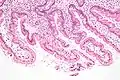

Microanatomy

Under microscopy, the duodenum has a villous mucosa. This is distinct from the mucosa of the pylorus, which directly joins to the duodenum. Like other structures of the gastrointestinal tract, the duodenum has a mucosa, submucosa, muscularis externa, and adventitia. Glands line the duodenum, known as Brunner's glands, which secrete mucus and bicarbonate in order to neutralise stomach acids. These are distinct glands not found in the ileum or jejunum, the other parts of the small intestine.[7] :274–275

The villi of the duodenum have a leafy-looking appearance, which is a histologically identifiable structure. Brunner's glands, which secrete mucus, are found in the duodenum only. The duodenum wall consists of a very thin layer of cells that form the muscularis mucosae.